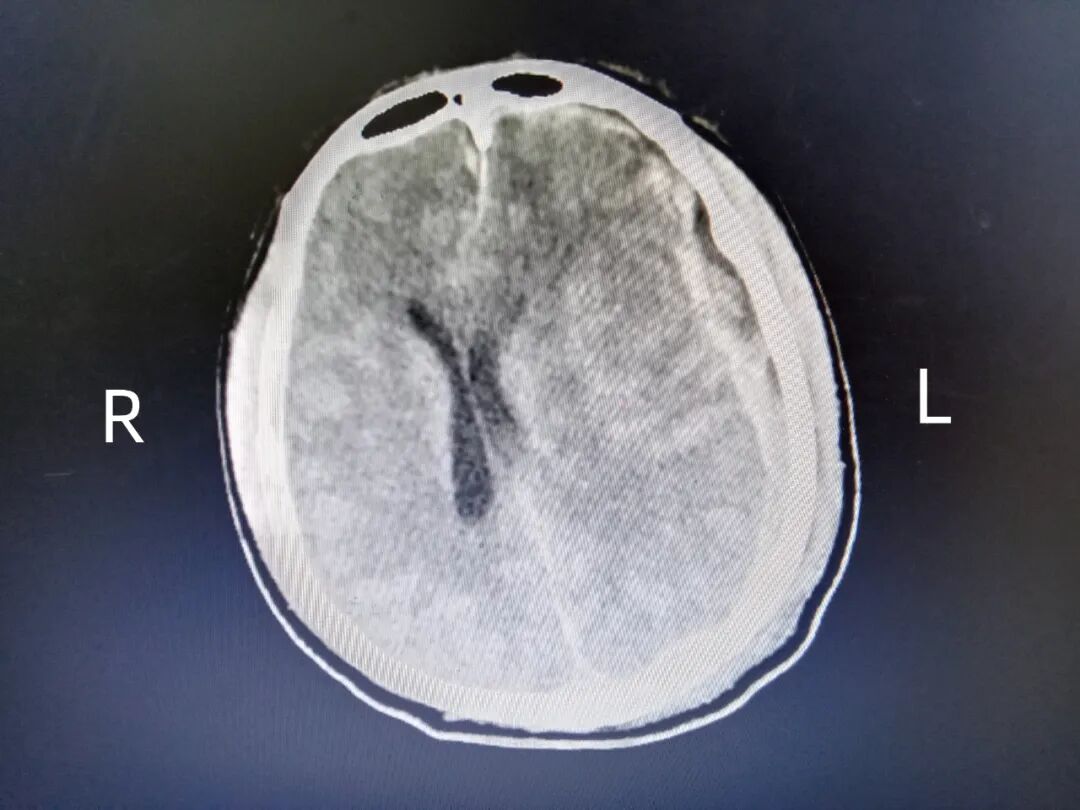

图左侧额叶出血

刚刚回到科室的万主任和宋医生,连忙放下手中还未动几口的盒饭,再次为患者复查CT,结果显示左侧额叶挫伤出血及脑疝。于是他们再次行额叶病灶及血肿清除,直到晚上9点结束治疗后,万主任和宋医生才得以稍作休息,他们虽然疲惫,但仍然心系患者,以医者大爱护佑患者生命健康。